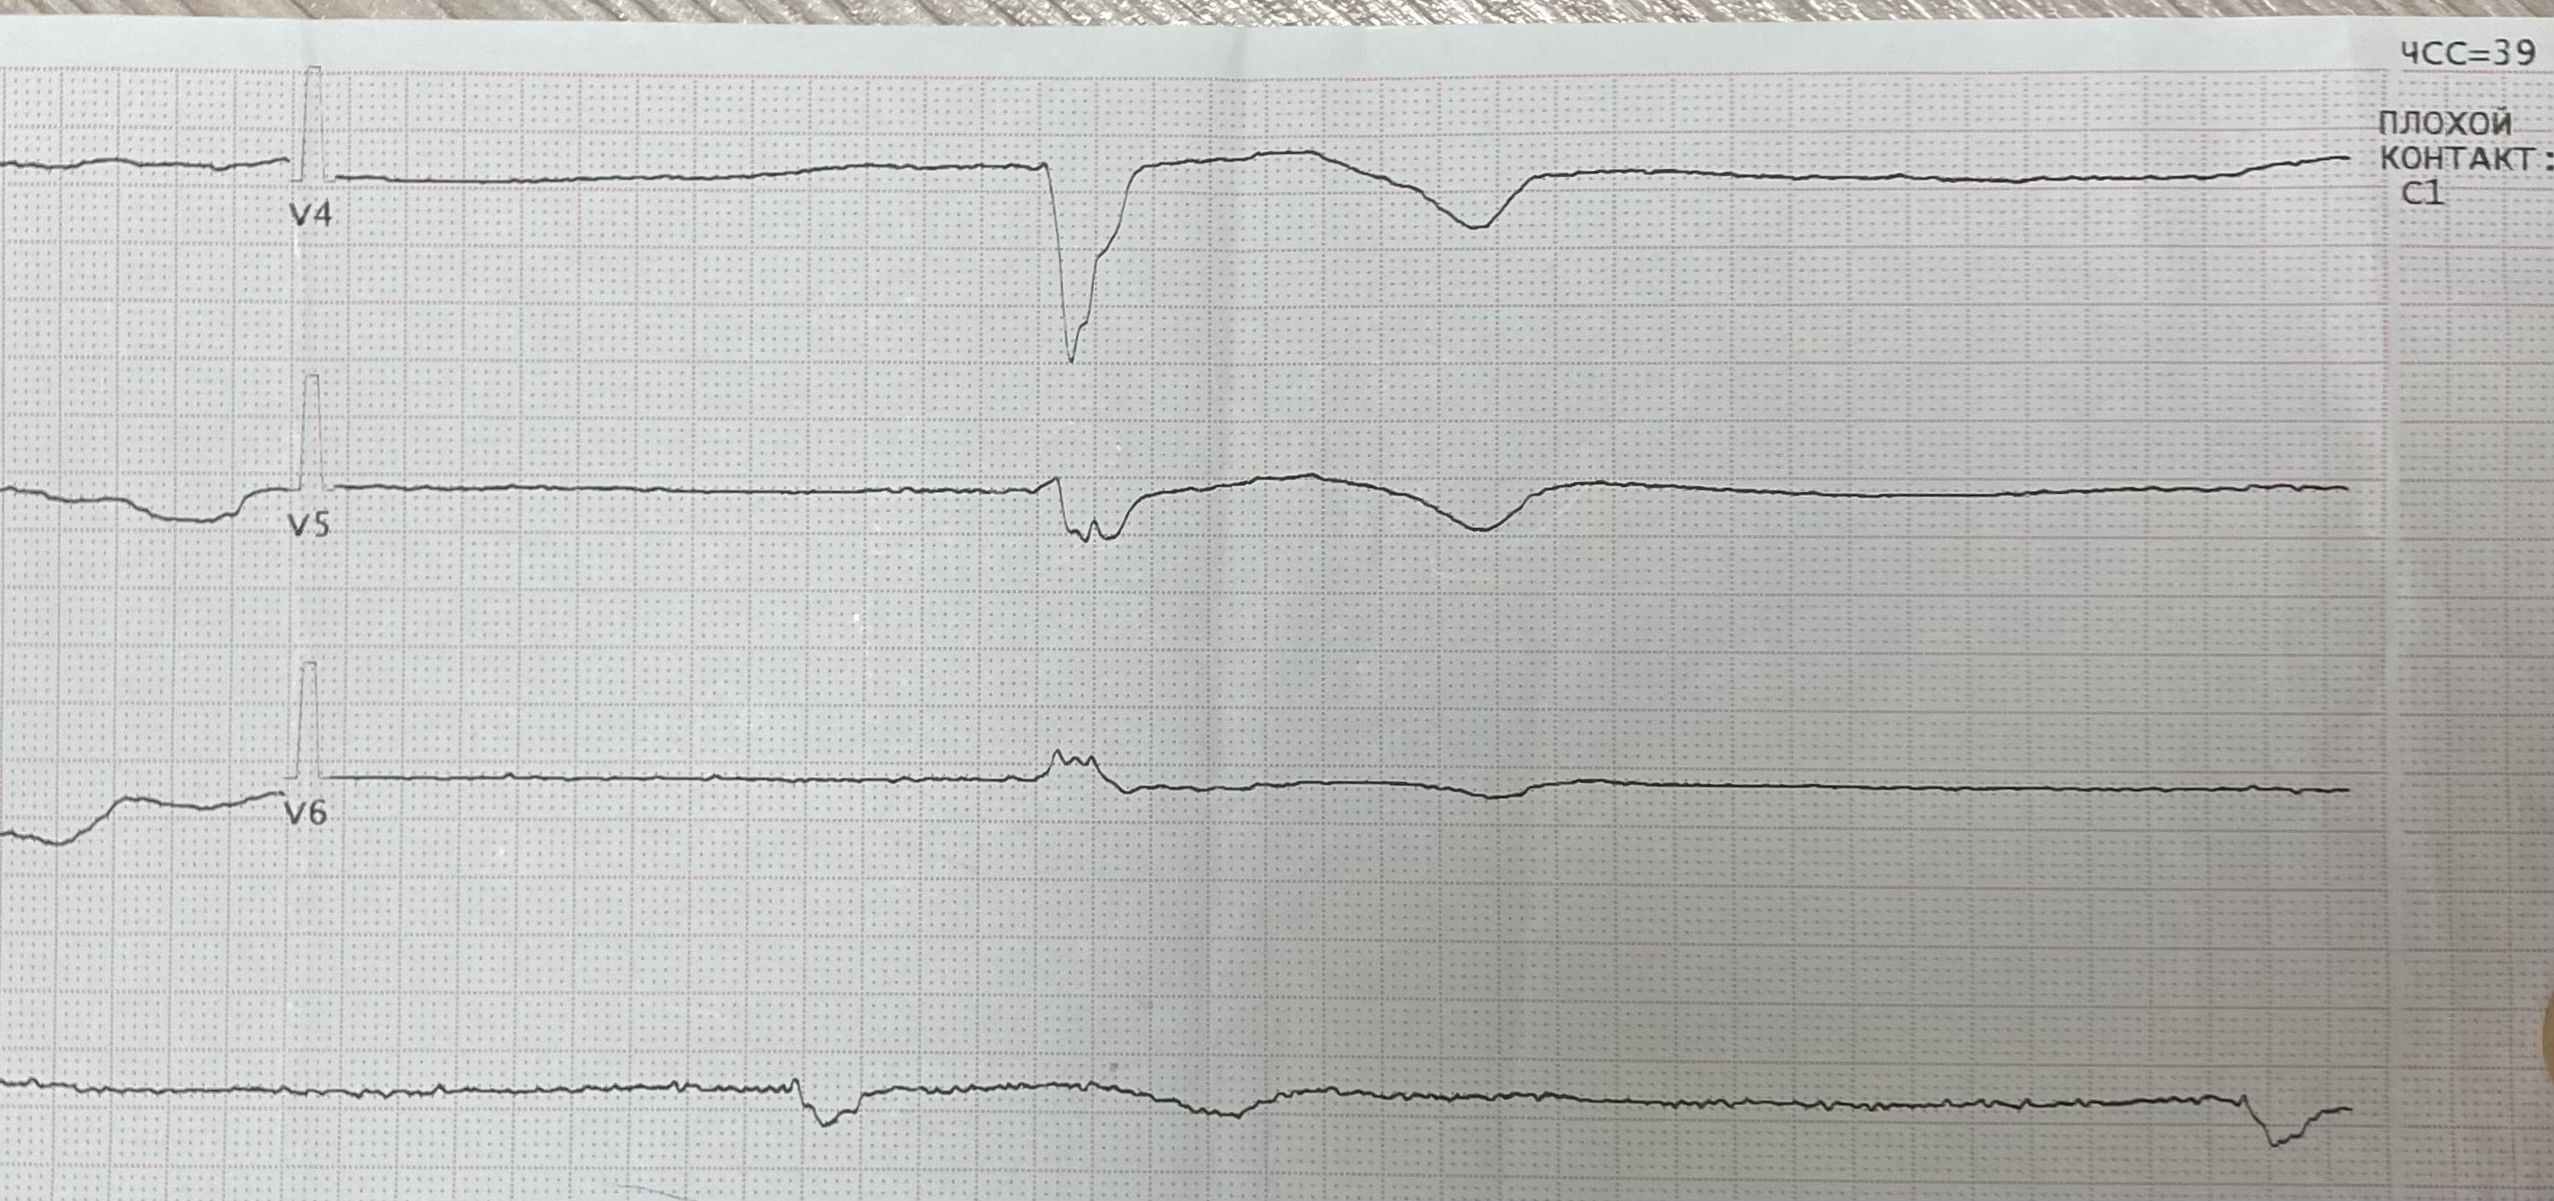

Заголовок сообщения: Синдром Фредерика

Обсуждалось здесь https://vk.com/club84409679?w=wall-84409679_13341%2Fall

IMG_0791.jpg

IMG_0791.jpg [ 775.29 KiB | Просмотров: 28906 ]

IMG_0792.jpg

IMG_0792.jpg [ 1.54 MiB | Просмотров: 28906 ]

IMG_0793.jpg

IMG_0793.jpg [ 1.13 MiB | Просмотров: 28906 ]

IMG_0794.jpg

IMG_0794.jpg [ 756.31 KiB | Просмотров: 28906 ]